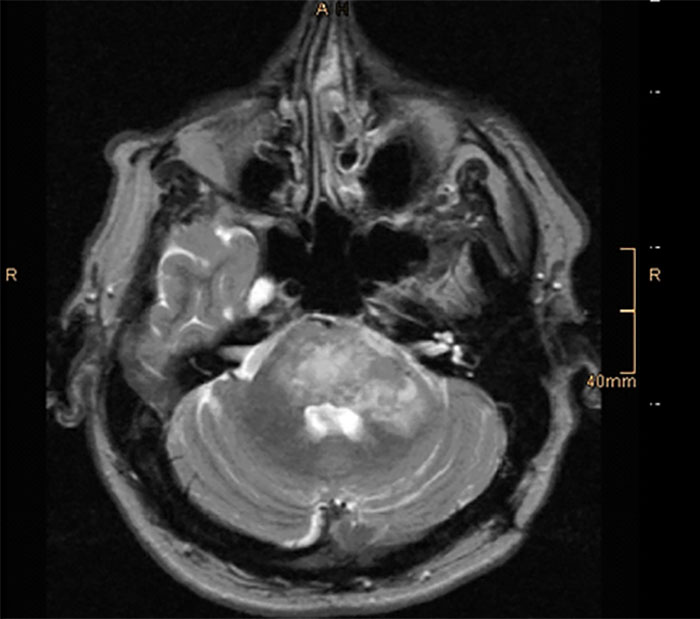

Load More Replies...There is an unknown object in my brain. MRI's revealed it. Tests for cancer were inconclusive. It Could be a tumor, a cyst, or something else.